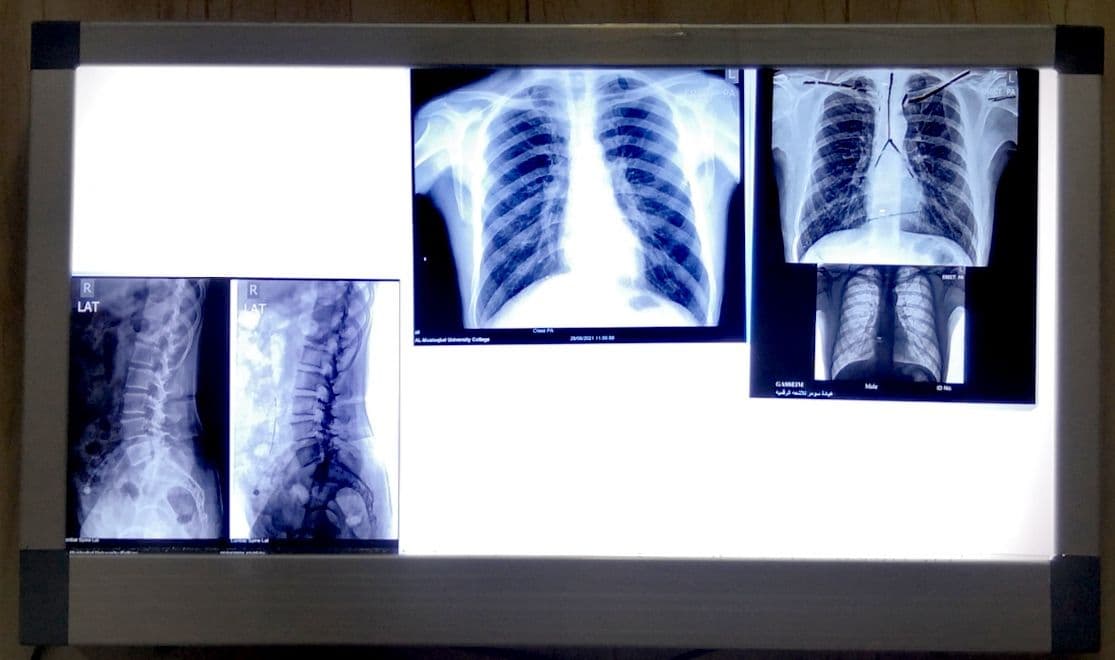

للتحقيق اهداف التنمية المستدامة (وقاية العاملين في مجال الاشعاع انفسهم من مخاطر الاشعاع) م.م انسام فاضل

مختبر التصوير الشعاعي والفحوصات الخاصة مرحله ثانيه وثالثه /فيزياوي كرار حيدر

مرض كورونا (كوفيد_١٩) واعراضه وتوعية الطلاب بأنواع القاحات المرخصة من قبل وزاره الصحة والحث على اخذ القاح .من أجل تحقيق أهداف التنمية المستدامة ( الهدف الثالث) م.م. أسراء رافد عباس